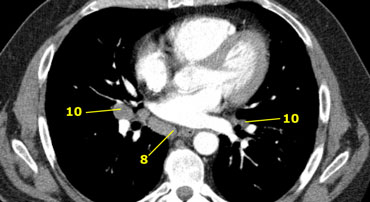

8 Paraesophageal nodes

These nodes are below the carinal nodes and extend caudally to the diafragm.

On the left an image below the carina.

To the right of the esophagus a station 8 node.

10 Hilar nodes

Hilar nodes are proximal lobar nodes, distal to the mediastinal pleural reflection and nodes adjacent to the intermediate bronchus on the right.

Nodes in station 10 - 14 are all N1-nodes, since they are not located in the mediastinum.